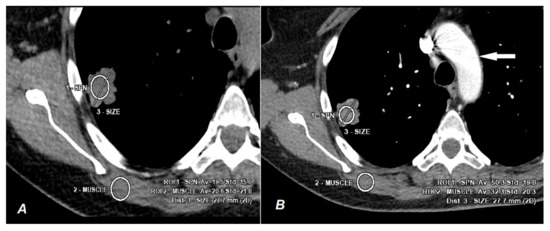

2. Materials and Methods

2.2. CT Scanning Parameters

2.3. Data Analyses